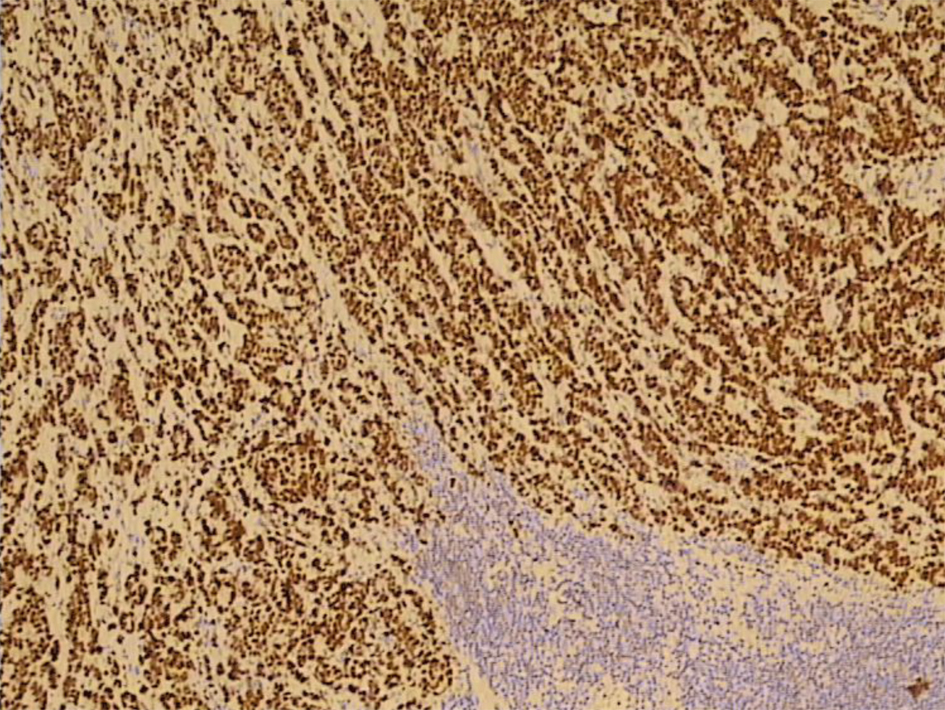

Three months before the admission to our clinic the patient underwent cholecystectomy with the extirpation of two lymph nodes of the hepatoduodenal ligament. Histological analysis of the extirpated lymph nodes showed infiltration with tubular formations and clusters of atypical epithelial cells which infiltrated the lymph node’s capsule (Fig. 1). Immunohistochemically, tumors cells showed a strong positive nuclear reaction to estrogen receptor in 100% of tumor cells (Fig. 2) and a moderate-to-strong reaction to progesterone receptor in 60% of tumor cells (Fig. 3). HER-2 receptor was negative, and proliferation index Ki67 was 60%. These results proved metastases of breast cancer cells into the extirpated lymph nodes.

![]() Click for large image | Figure 2. A strong positive nuclear reaction to estrogen receptor in 100% of tumor cells (IMH, × 10). |